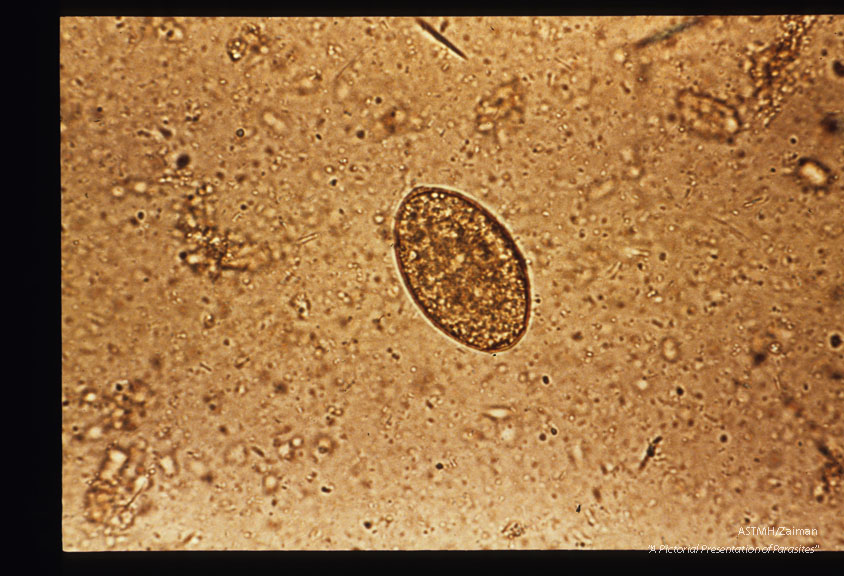

Egg in stool. Iodine stained.

Diphyllobothrium laturn

Description: Egg in stool. Iodine stained.